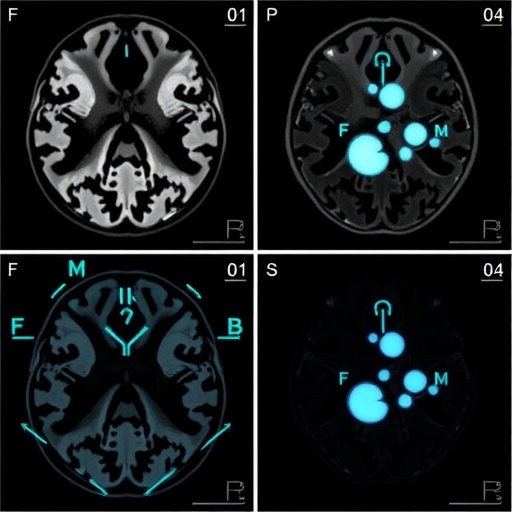

The integration of high-field MRI systems (0.55-3T) is another focal point of this research. These systems provide enhanced signal-to-noise ratios and better image quality, facilitating the detailed assessment of brain structures such as the cortex, ventricles, and cerebellum. The researchers implemented sophisticated algorithms to analyze these complex images, aiming to retrieve critical biometric information without the manual intervention that could introduce biases or inaccuracies.